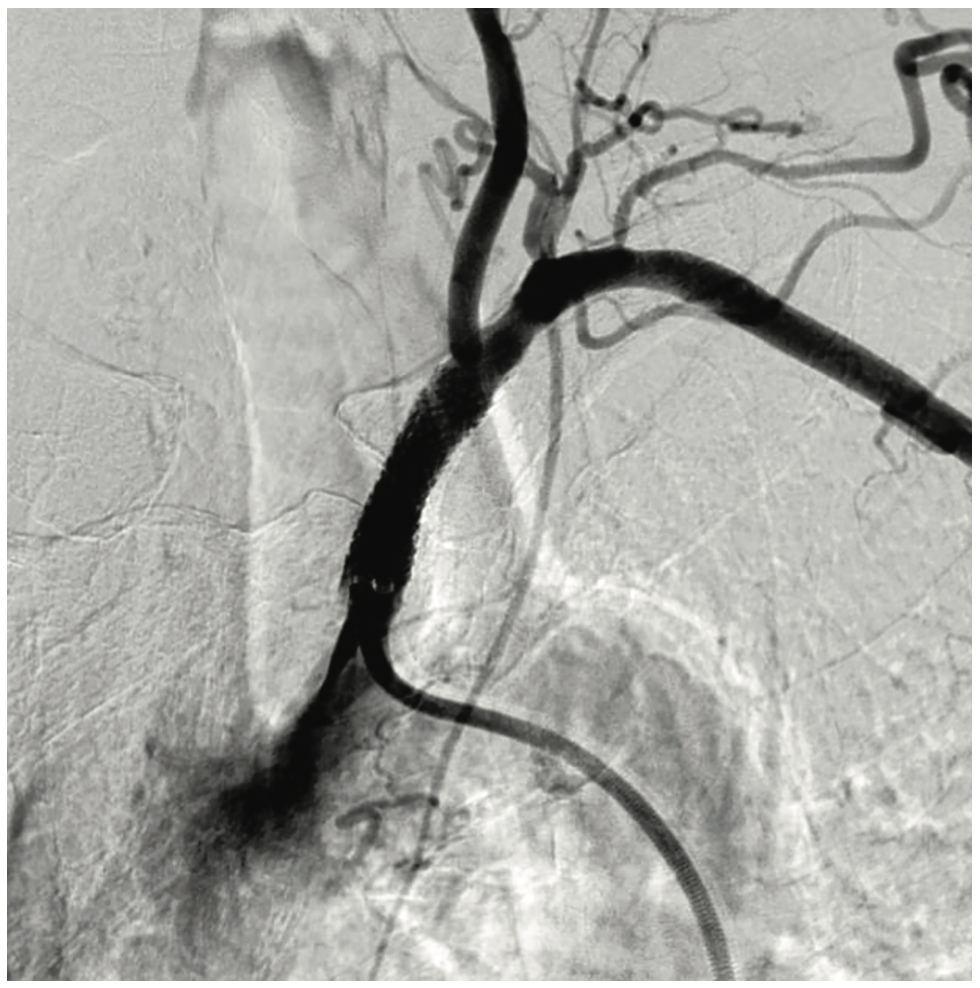

A 77-year-old female with a past medical history significant for chronic obstructive pulmonary disease, hypertension, hyperlipidemia, mild obesity, insomnia, hypothyroidism, and depression presented with progressive dizziness and increasing pain in the left arm and forearm. A peripheral angiogram revealed left subclavian stenosis diagnosed as subclavian steal syndrome (Figure 1). On the night of admission, she underwent catheterization for the removal of the clot (Figures 2-3). During the procedure, a piece of the clot embolized down to the left upper extremity. On physical examination, her skin was mottled, and no pulses were detected in the left ulnar and radial arteries. Her left-hand grip was also weak. Given these findings, she underwent another catheterization to remove a 4.0 mm clot in the left brachial artery (Figures 4-5). During the angioplasty, the brachial clot reformed despite many attempts at removal and tPA administration. Vascular surgery was consulted. As a result of the clot, the patient had developed compartment syndrome, and her cardiologist advised the family to consent to a thrombectomy and fasciotomy. During the procedure, a clot was removed from both the ulnar and radial arteries, and pressure in the forearm was relieved (Figure 6). An angiogram revealed patent radial and ulnar arteries, and flow was detected in the palmar arch (Figure 7). Upon completion of the procedure, the patient had palpable radial and ulnar pulses. The flexor muscles of the forearm were dusky but viable and responded with contraction to electrocautery.